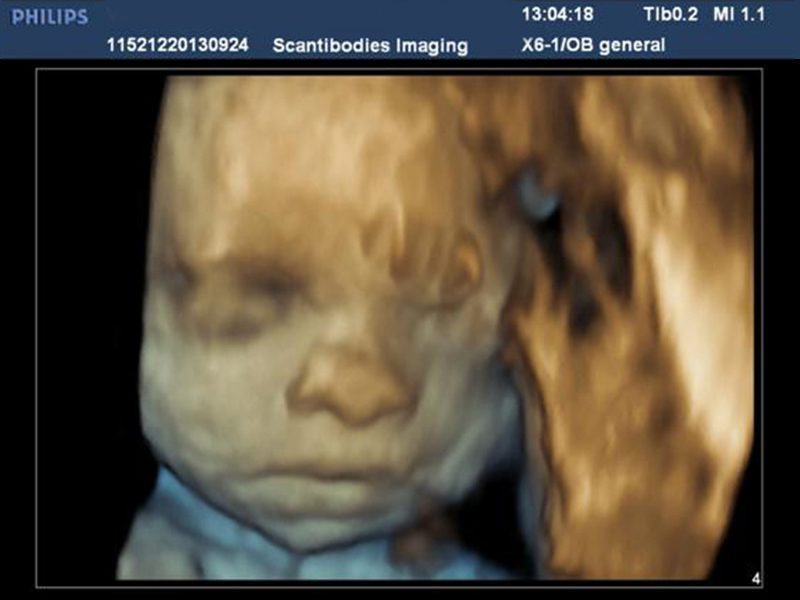

El ultrasonido iU22 xMatrix es un sistema que provee imágenes nítidas de alta resolución, y calidad única en 2D, 3D Y 4D de un mismo transductor. Provee una perspectiva clara durante las biopsias y ablaciones. El equipo tiene la capacidad de realizar el estudio de elastografía mamaria.

Ultrasonidos obstétricos 3D - 4D